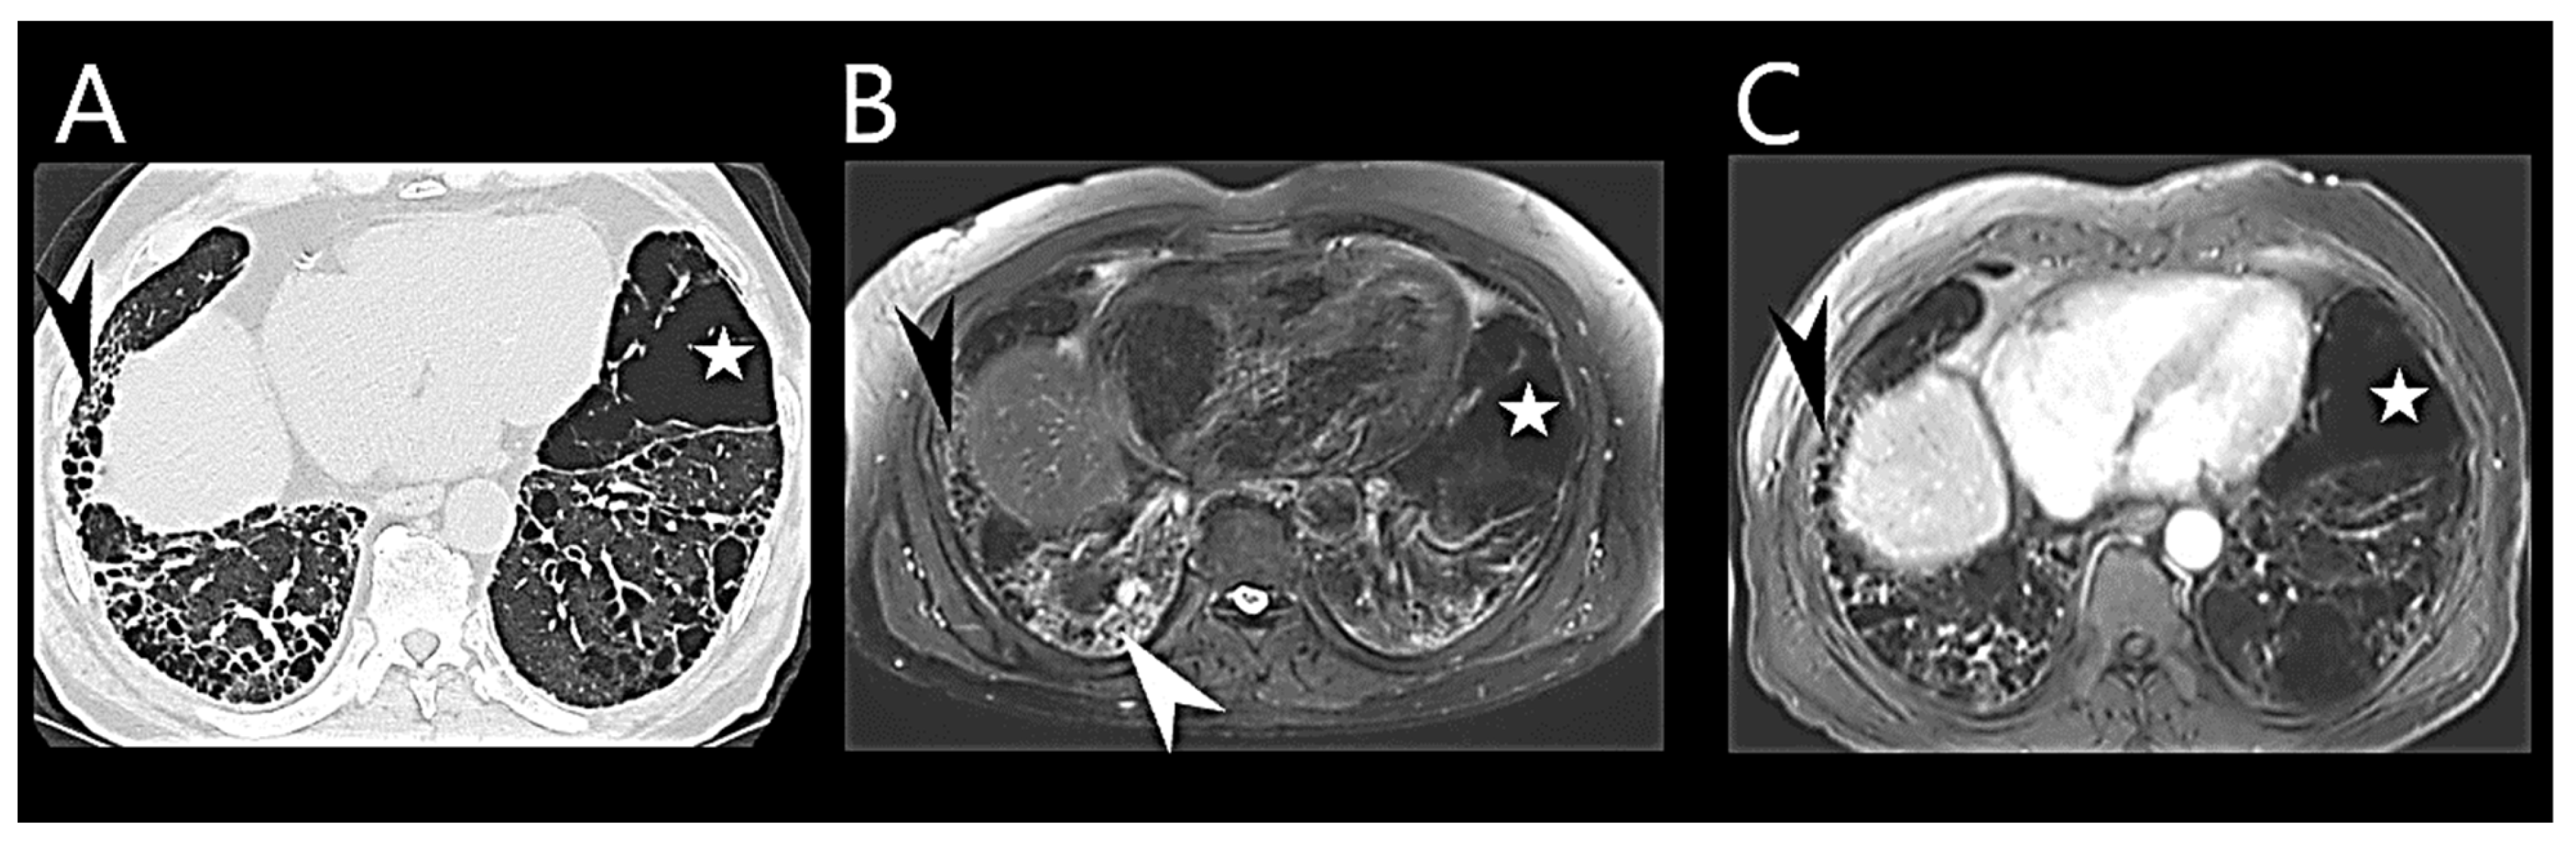

3. PH-ILD Disease Spectrum

4. PH-ILD Phenotypes

- Hage, R.; Gautschi, F.; Steinack, C.; Schuurmans, M.M. Combined Pulmonary Fibrosis and Emphysema (CPFE) Clinical Features and Management. Int. J. Chronic Obstr. Pulm. Dis. 2021, 16, 167–177. [Google Scholar] [CrossRef]

- Ryerson, C.J.; Hartman, T.; Elicker, B.M.; Ley, B.; Lee, J.S.; Abbritti, M.; Jones, K.D.; King, T.E.; Ryu, J.; Collard, H.R. Clinical Features and Outcomes in Combined Pulmonary Fibrosis and Emphysema in Idiopathic Pulmonary Fibrosis. Chest 2013, 144, 234–240. [Google Scholar] [CrossRef]

- Tomioka, H.; Mamesaya, N.; Yamashita, S.; Kida, Y.; Kaneko, M.; Sakai, H. Combined pulmonary fibrosis and emphysema: Effect of pulmonary rehabilitation in comparison with chronic obstructive pulmonary disease. BMJ Open Respir. Res. 2016, 3, e000099. [Google Scholar] [CrossRef] [PubMed]

- Sato, T.; Tsujino, I.; Tanino, M.; Ohira, H.; Nishimura, M. Broad and heterogeneous vasculopathy in pulmonary fibrosis and emphysema with pulmonary hypertension. Respirol. Case Rep. 2013, 1, 10–13. [Google Scholar] [CrossRef] [PubMed]

- Cottin, V.; Le Pavec, J.; Prevot, G.; Mal, H.; Humbert, M.; Simonneau, G.; Cordier, J.-F. Pulmonary hypertension in patients with combined pulmonary fibrosis and emphysema syndrome. Eur. Respir. J. 2010, 35, 105–111. [Google Scholar] [CrossRef] [PubMed]